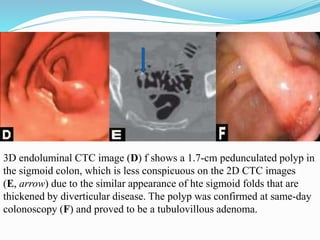

This document discusses colorectal polyps. It defines polyps and describes their types, including neoplastic and non-neoplastic polyps. It discusses adenomatous polyps in depth, noting their malignant potential increases with size over 1cm and villous architecture. Radiological diagnostic methods for polyps including single and double contrast barium enema and CT colonography are explained. The document provides an overview of polyp pathogenesis and genetic syndromes like FAP that increase cancer risk.